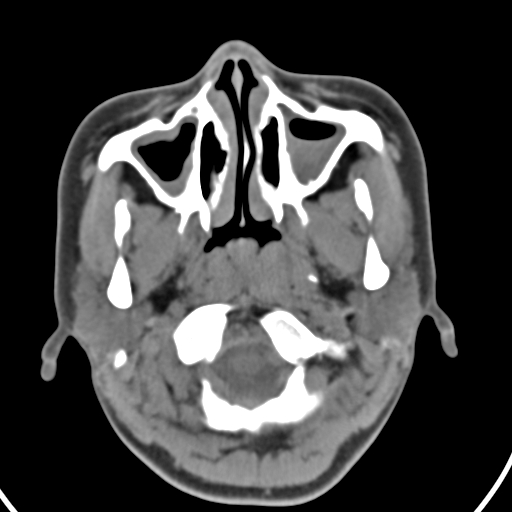

以下是引用zjzjr在2008-12-5 11:46:00的发言:[br]脂肪密度,壁有钙化.考虑口咽部皮样囊肿可能性大.双侧上颌窦炎,双侧下鼻甲粘膜肥厚.增殖腺肥大,扁桃体亦增大,考虑炎性.

以下是引用随光逐影在2008-12-5 18:27:00的发言:[br]1)考虑左侧茎突过长综合征并茎突舌骨韧带囊肿形成突入咽部;左侧咽部慢性炎症。2)鼻咽腺样体肥大。3)双侧扁桃体肿大。4)双侧上颌窦炎。5)双侧下鼻甲粘膜肥厚。